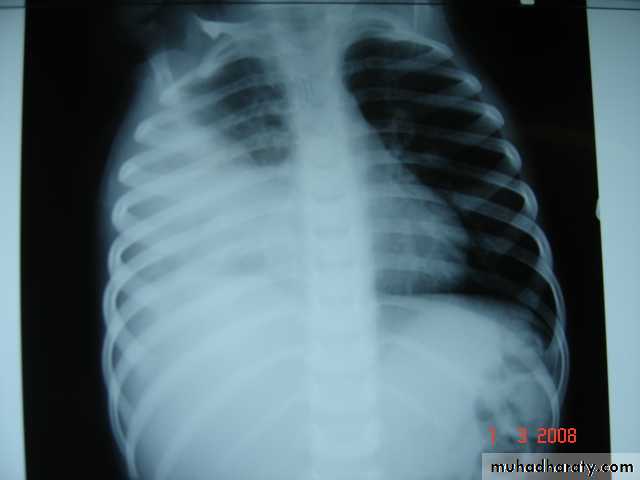

• 1-Spontaneous pneumothorax

Is the accumulation of air inside the pleural cavity , occurring without any known etiology .More in males ,more on the right side .It can be bilateral

• Causes 1- Ruptured pulmonary bleb.2-Ruptured of a cystic defect in the pleura.3-Teared visceral pleura 4-No cause can be demonstrated in (15-20%).Complications:-1-pleural effusion2-empyema 3-tension pneumothorax which leads to mediastinal shift &circulatory collapse.4-Respiratory failure in elderly patient with COAD (COPD) .